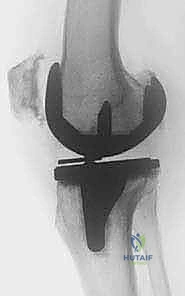

الخطوة السادسة: تركيب المفصل الجديد المُخصص للمراجعة

يتم استخدام مفاصل مراجعة خاصة تحتوي على سيقان معدنية تمتد داخل العظم لزيادة الثبات، ووسائد بلاستيكية (Polyethylene) ذات تقييد أعلى لضمان استقرار الركبة ومنع خلعها. يتم تثبيت المكونات بالزوايا الصحيحة تماماً لضمان حركة سلسة.

| المكونات المستخدمة | مفصل ركبة قياسي | مفصل مراجعة مع سيقان داعمة ودعامات عظمية معدنية |

| التعامل مع الأنسجة | روتيني | يتطلب استئصال جذري للأنسجة الندبية وتحرير الأربطة |